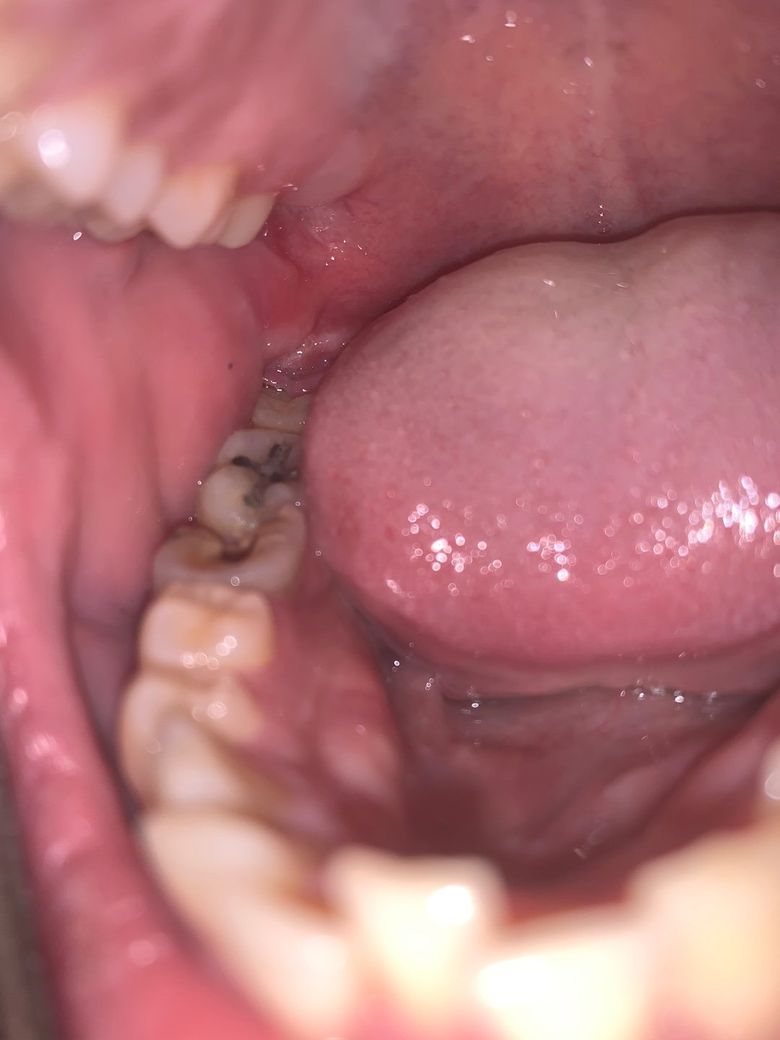

말씀하신 치아 주변으로 염증이 있을 가능성이 매우 높습니다. 보통 한쪽 염증이 심한 경우에는 해당 부위쪽 림프절이 비대해지거나 통증이 생기고 침을 삼킬때도 해당 부위에 통증이 나타날 수 있습니다. 심한 경우에는 비슷한 부위쪽 전체 통증으로 나타날 수 있습니다. 지금 상황으로 보아서는 염증 단계를 넘어 농양일 가능성도 있으므로 치과 방문 후 해당 부위에 대한 치료를 해야 할 것으로 보입니다. 심할 경우에는 배농을 하셔야 합니다. (농을 빼내는 치료)

심하게 부종이 있는것으로 보입니다.

우선 정확한것은 방사선사진을 찍어봐야 알겠지만, 현재 해당치아에 치근단농양이 형성되었을 가능성이높습니다.

이런경우 농이 차면서 심하게 붓고 아플 수 있습니다.